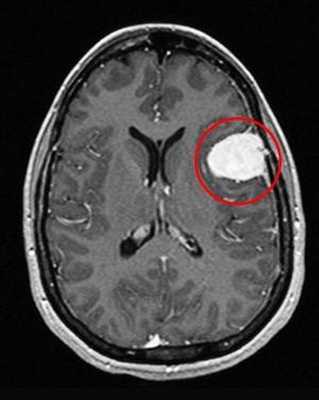

Как же узнать, есть ли на снимках признаки болезни? Самое главное - запомнить, как выглядит головной мозг здорового человека. Врач, изучая снимки пациентов, постоянно сравнивает их с нормальными снимками, хранящимися у него в голове. Чтобы понять, как это происходит - посмотрите на снимки внизу:

Перед вами - два снимка, сделанных в одном режиме. Снимок снизу - норма. Какое заболевание, в таком случае, есть на верхнем снимке? Чтобы понять это, нужно сравнить эти изображения. Явно видно отличие - на верхнем снимке в правой части головного мозга есть новообразование. Разница еще заметнее, если сравнить левую и правую части того же снимка.

Отметим его красной окружностью. Визуально оно представляет собой узел, неоднородный по окраске и отличающийся от серого и белого вещества головного мозга. В таких случаях, чтобы точно определить границы опухоли и определить её тип исследование повторяют с контрастом. Введение контрастного препарата в кровь через локтевую вену приводит к накоплению контрастного вещества в тканях опухоли - нормальные здоровые ткани его практически не накапливают. И мы получаем следующую картину, показанную на рисунке справа. Яркая окраска опухоли соответствует накопленному контрасту - теперь можно не только сказать, где опухоль, но и примерно определить, что это доброкачественная опухоль, так как она имеет четкие границы (злокачественные опухоли прорастают окружающие ткани, из-за чего границы будут размытыми и не такими четкими).